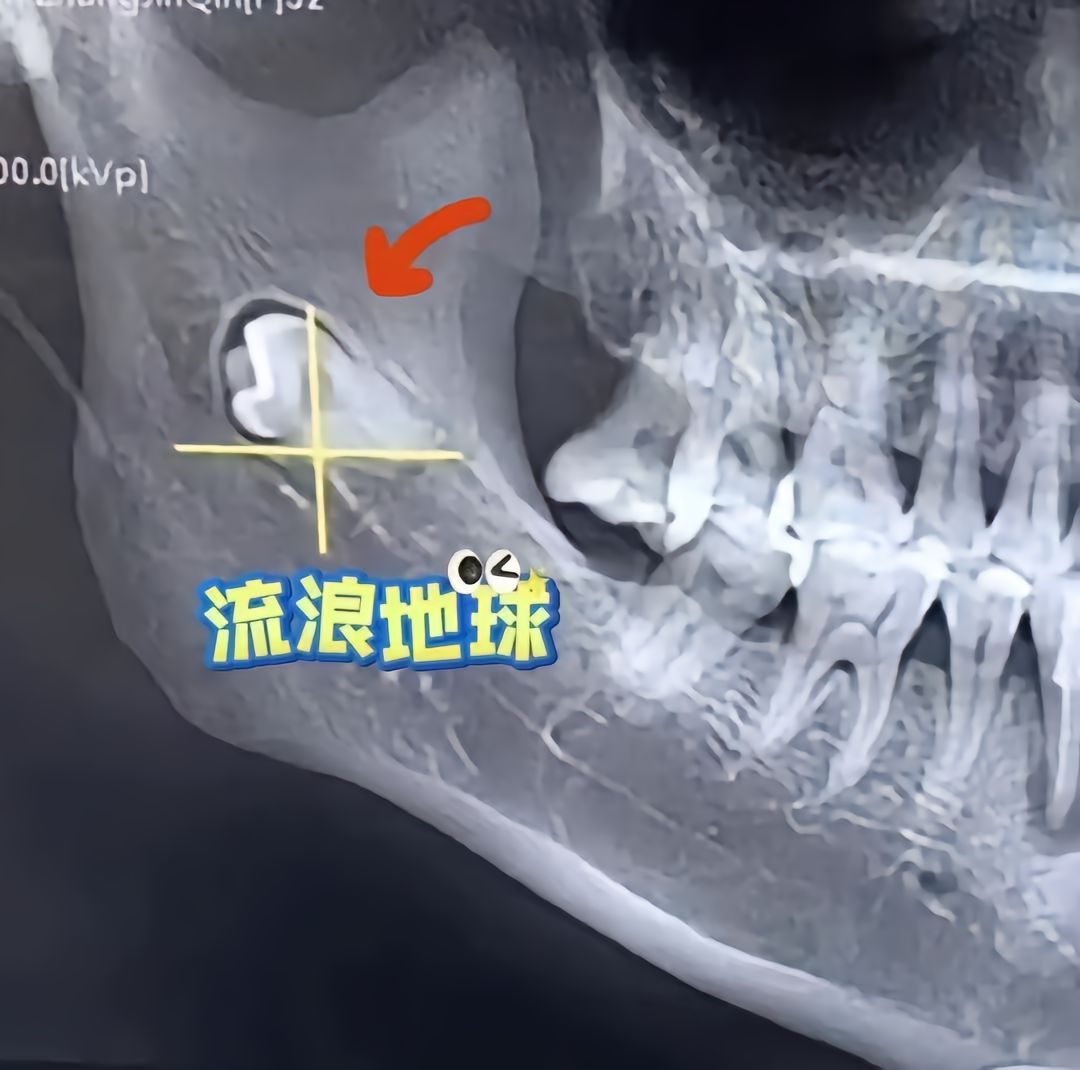

各种各样生长的牙齿